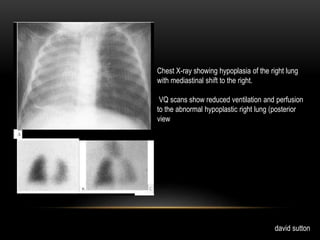

Chest X-ray showing hypoplasia of the right lung

with mediastinal shift to the right.

VQ scans show reduced ventilation and perfusion

to the abnormal hypoplastic right lung (posterior

view